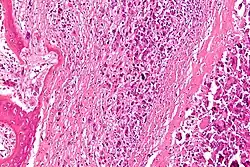

Een bottumor of beentumor is een plaatselijke abnormale groei van cellen in het bot. Bottumoren (of botgezwellen) kunnen goedaardig (benigne) zijn of kwaadaardig (maligne).

Een tumor heet kwaadaardig als hij de eigenschap heeft om in te groeien in het omliggende weefsel (infiltratie) en uit te zaaien (metastasering).